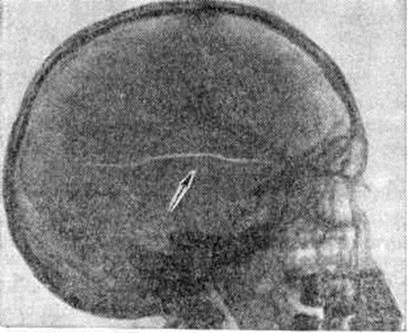

Рис. 11.

Боковая рентгенограмма черепа: перелом височной кости (указан стрелкой).